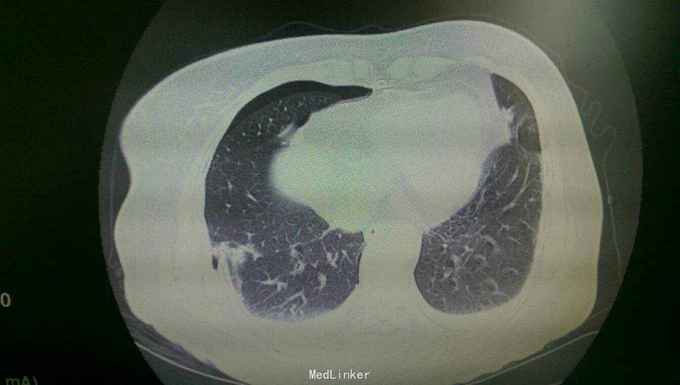

查体:体温36.2,脉搏104次/分,呼吸22次/分,血压80/40mmhg。患者嗜睡,急病容,痛苦貌。右额顶部巨大头皮血中,伴头皮挫裂伤,有出血。瞳孔等大,光反存在。耳鼻,口腔无出血。气管居中。右侧胸廓畸形,胸廓挤压痛明显。右侧呼吸音低,可闻及湿啰音。心率104次/分,律齐。未闻及病理性杂音。腹部平软,全腹无压痛,肠鸣音存在,腹腔穿刺未抽出血性液体。肾区叩击痛阴性。胸腰椎有明显压痛。四肢无畸形,活动可。神经系统无异常。 辅查:头颅ct示:外伤性蛛血,右额顶部巨大血肿。胸部ct示:右第3--12肋骨折(8-10骨折端明显错位,并见骨折端刺入右下肺组织),左8-9肋骨折。伴右肺上下叶及左上叶肺挫伤。双侧液气胸。右胸壁皮下气肿。胸椎9-11棘突骨折,胸11椎体骨折可能,腰1-2右横突骨折。

患者拟诊为:严重多发伤,创伤性失血性休克。严重胸部外伤,双侧多发肋骨骨折,双侧血气胸,肺挫裂伤。外伤性蛛血,头皮挫裂伤胸腰椎多处骨折。 患者来院后即给于输液等抗休克并在急诊术前准备完毕后,送手术室行急诊右侧剖胸探查,左侧胸腔闭式引流术。术中见血性液体1500ml,探见右下肺二处裂口,各长约二公分,有血性气体溢出,行肺修补术。多根肋骨错位,给于复位后,部分肋骨用爪形钢板行胸壁固定。左侧闭式引流出约500ml血性液。手术顺利,术后病人送icu继续救治,目前病人病情稳定,已转普通病房进一步输液,抗炎,化痰,支持等治疗。